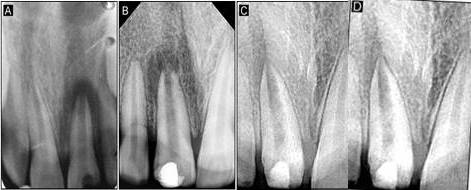

A 12-year-old male patient reported to the Department of Pedodontics and Preventive Dentistry with a chief complaint of fractured upper front tooth. The patient had a history of trauma to tooth #11 two years back. Upon clinical examination, the patient was asymptomatic, and the tooth #11 with Ellis class IV fracture exhibited no response to thermal and electric pulp testing. Radiographically open apex in association with periapical lesion of approximately 2 mm in diameter was seen in #11 (Figure 6a). To promote faster healing, we planned to attempt and achieve regeneration of periapical tissues and pulp by tissue engineering technique with his parental consent. Access opening was prepared and the necrotic pulp tissue was removed (Figure 5a). The root canal was thoroughly irrigated with normal saline solution and dried using absorbent paper points. Then, the scaffold PerioGlas® (bioglass) was introduced into the canal, followed by homing of SHED (Figure 5b) and the cavity was sealed with a glass-ionomer cement of 5 mm thickness. The patient was scheduled for review examination and advised to call if he felt pain. The patient returned after 7 days; he was asymptomatic, reporting no pain to percussion tests (Figure 6b). In the 30-day review, the patient was asymptomatic, and showed no signs of pain. The radiograph showed complete resolution of periapical radiolucency and the closure of apex with thickening of dentinal walls in relation to tooth #11 which continued until the 365-day follow-up period (Figures 6c and 6d). Electric pulp testing was found to be positive for the treated tooth #11 from the 3-month recall to 12-month follow-up.

Figure 5.a. Access opening of tooth #11; b. Homing of stem cells into tooth #11.

Figure 6.A: Preoperative radiograph displaying periapical radiolucency in relation to tooth #11; B: 7-day postoperative radiograph; C: 30-days follow-up radiograph showing complete radiolucency in relation to tooth #11. D: 365-day follow-up radiograph.